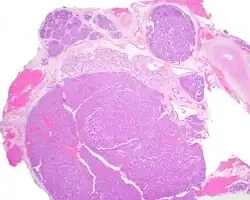

Canalicular adenoma is a type of growth that occurs in human salivary glands. It is a benign growth which occurs in the epithelial cells, and is typically arranged in columns of cells that form interconnecting cords. Canalicular adenoma is a very rare benign neoplasm; it constitutes about 1% of all salivary gland tumors and about 4% of all benign salivary gland tumors.[1][2]

Canalicular adenoma is most common in patients age 70 to 80, with females affected about four times as often as males. Most growths present in the upper lip; some also occur in the a few present in palate or buccal (cheek) tissue as a slowly enlarging mass.[3] The growths will often arise in multiple places at the same time or develop multiple nodes, despite not being clinically invasive or malignant.[1][4]

Canalicular adenoma growths are usually small at the time they are noticed, with an average size of about 1.6 cm.[1] Their histologic appearance is very distinct, with a channel-like pattern between cords and ribbons; the pattern has been described as resembling a "string of pearls."

The growths often contain are often small bight squamous balls, or morules. They also typically contain a well-developed supporting tissue - a fibrous stroma - which is rich in hyaluronic acid and chondroitin sulphate.[1] In a few cases, the growths may contain small calcium deposits or microliths. Although it is seldom necessary, a pathologist can confirm the existence of canalicular adenoma through immunohistochemistry studies, with the cells reacting with pancytokeratin, S100 protein and SOX10, with a delicate GFAP reaction around the periphery.[5][1][6][7] Although it is a benign tumor, a positive diagnosis of canalicular adenoma may be necessary to exclude the existence of other medical conditions such as a basal cell adenoma, pleomorphic adenoma, adenoid cystic carcinoma, and polymorphous adenocarcinoma.